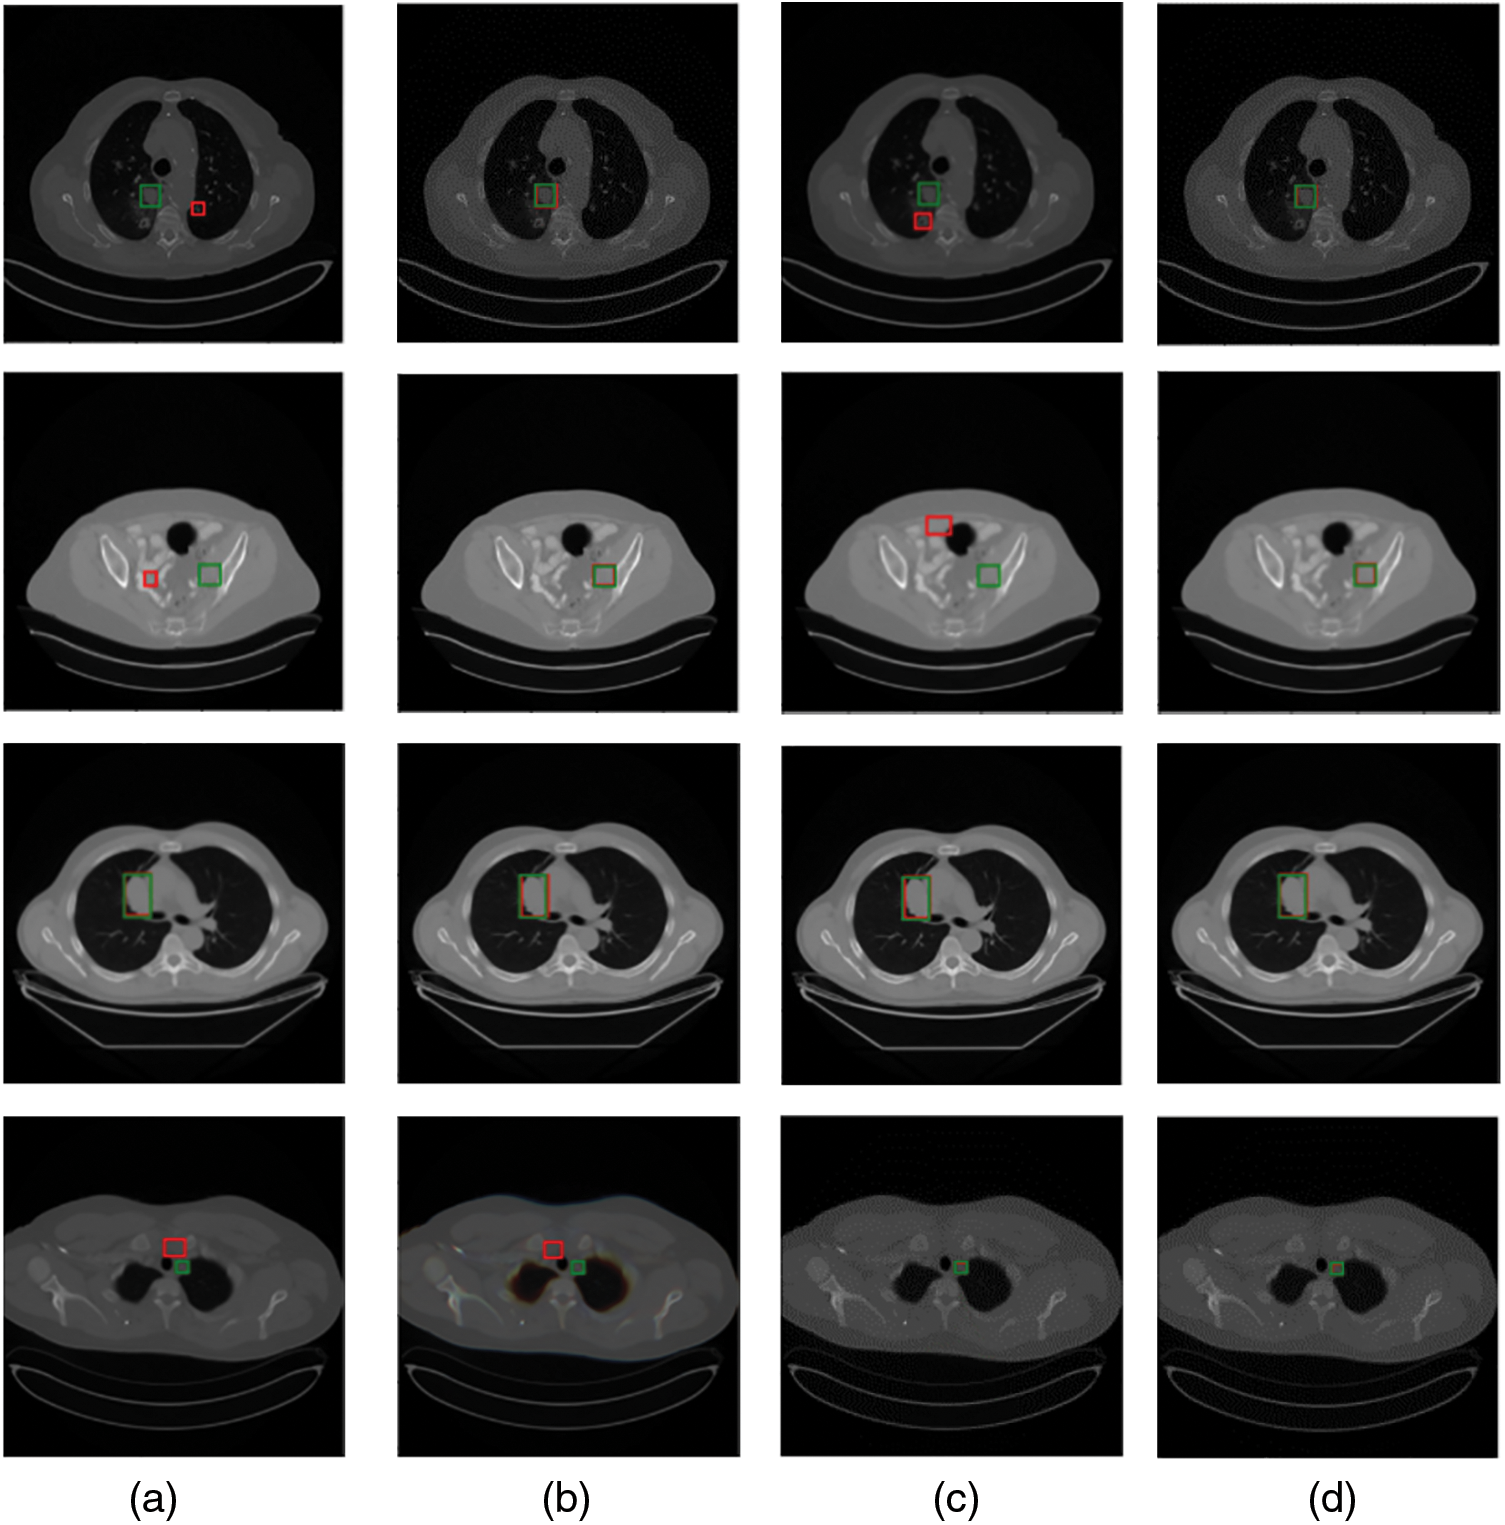

We show the effectiveness of several methods for detecting single-organ lesions on a multi-organ lesion detection task in Fig. 1. We can see that a universal lesion detection network has more potential and values. Inspired by camouflaged object detection in video [17], enhancing the temporal correlation of multiple sequential slices contributes to the capture of lesions between slices by the network. Accordingly, by enhancing the temporal correlation, the feature representation of slices can be improved for improving the detection accuracy. Through the above observation, we find that the existing universal lesion detection methods neglect to focus on the correlation between CT slices, which can provide richer features for complex lesion detection tasks. Therefore, we propose an enhanced temporal correlation detection network (i.e., TCE-Net), in which the temporal correlation enhancement (TCE) module is introduced to extract temporal correlations of multiple sequential CT slices. In addition, multi-scale feature maps of sequential slices are extracted using a pre-trained Feature Pyramid Network (FPN) [31] for detecting lesions of different sizes.

Figure 1: Comparison of visualization results of several single organ detection networks with ours. Green and red boxes correspond to ground-truths in the test set and predicted true positives. (a) The method proposed in [37]; (b) a modified SSD model by [38]; (c) MSCR [39]; (d) ours